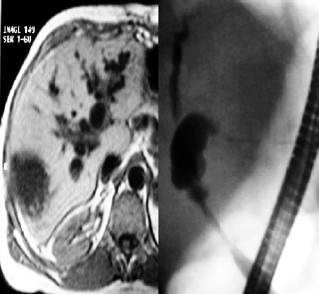

- Biliary leaks: bile leaking from biliary duct whether or not at site of anastomosis (Figure 3)-

- Other complications found: Lithiasis, biliary sludge, bilomas (Figure 4), and Sphincter of Oddi dysfunctions.

Figure 3. Mild anastomotic stenosis with local biliary leakage, endoscopically managed with CPRE and placement of a plastic stent.

Figure 4. Multiple bilomas in the explanted liver in a patient with ischemic stenosis from anastomosis.